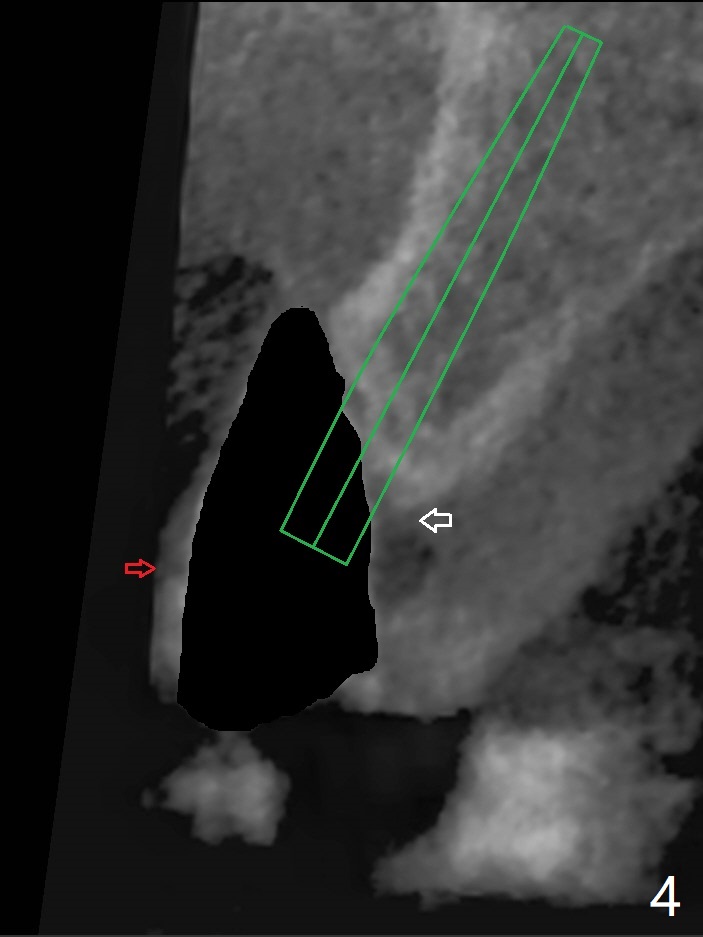

左上尖牙拔除前发现远中腭侧瘘道,拔除后发现相对牙槽嵴骨缺损(图一(术前CT):*),其实患牙根尖在颊侧骨板颊侧(图二:>),拔除后,根尖骨板缺损(图三:>),由于后者离颊侧牙槽嵴(图四:红箭头)远,骨粉修复重要性不如腭侧牙槽嵴(图四:白箭头),当窄植体植入后(图四:绿色),首先在腭侧植骨(图五:红圆圈),因为基台放置后(图六:粉红色),腭侧植骨开口狭窄(图六:白箭头)。即刻种植总是腭侧,颊侧间隙大,颊侧根尖缺损填骨应该容易(图七:橘黄色圆圈),即使不全(*),无关大局。徒手初步钻洞(图八),种植(图九)方向尚可,植骨好像完全(图十:*)。术后一周临时牙冠(11,尖牙)比侧切牙还短(图十一),随着愈合,尖牙牙冠会比双尖牙还短,因为植体偏腭侧,可能需要调整临时牙冠边缘。颊侧牙龈单纯疱疹感染,颊侧根尖仍有疼痛,腭侧瘘道缩小。